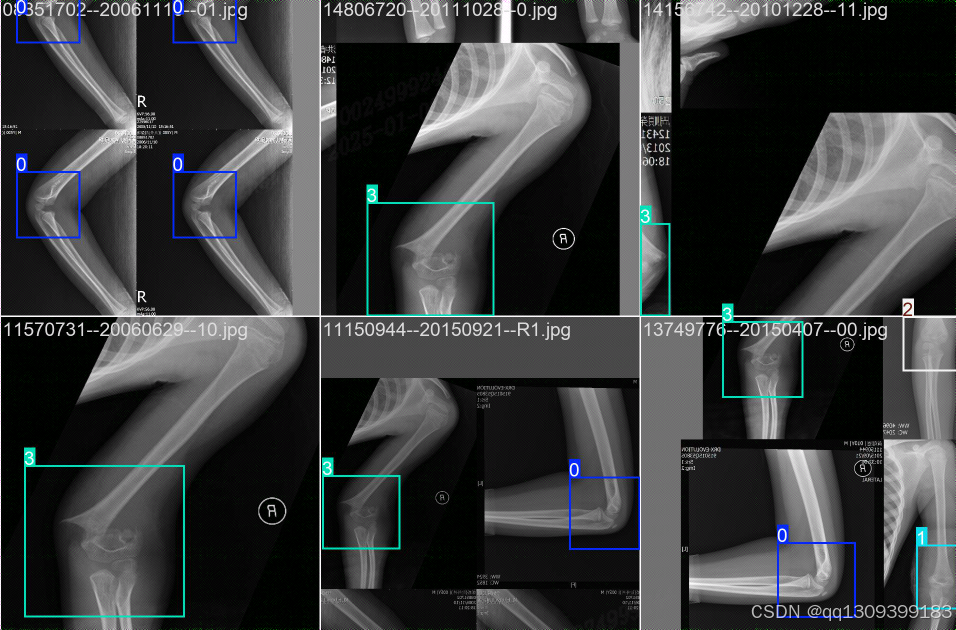

结果展示